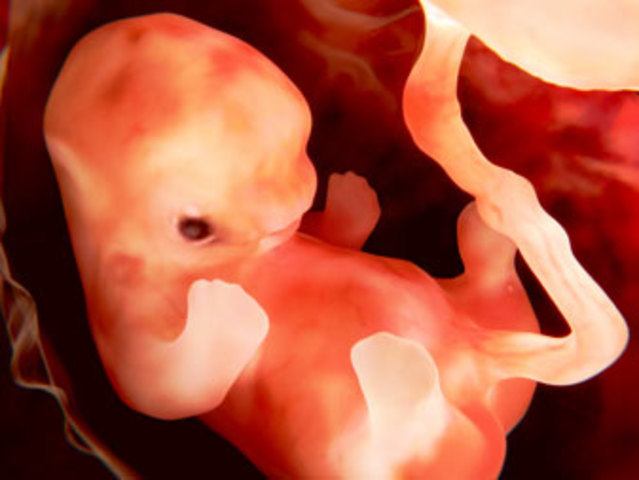

• Semana 6 y 7

Semana 6 y 7

Las yemas de brotes de brazos y piernas crecen. El corazón del embrión en la semana seis de embarazo está formándose y ya tiene dos vasos sanguíneos y ahora late a un ritmo regular. El cerebro se transforma en cinco áreas diferentes y algunos nervios craneales son visibles. Los oídos y ojos empiezan a formarse. los tejidos que se convertirán en columna y huesos empiezan a formarse. Tiene una estructura llamada surco genital que dará origen a las gónadas y una elevación llamada tubérculo genital.

• Semana 8

Semana 8

Los brazos y piernas se han alargado, sus manos y piernas comienzan a formarse y lucen como pequeños remos. El cerebro continua formándose; los pulmones ya empezaron a formarse. Ya hay una diferenciación sexual que fue determinada desde la fecundación.